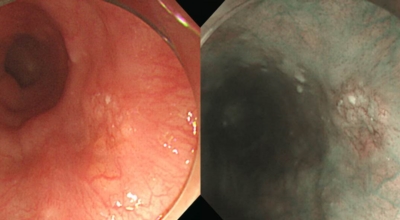

식도암은 다른암에 비해 사망률이 아주 높은 암이랍니다. 초기 발견 시에는 예후가 매우 좋지만, 2,3기에 발견될 시에는 사망률이 급격히 오르게 돼요. 다만 초기에는 증상이 거의 없으므로 문제가 됩니다. 초기에 관찰되는 경우는 내시경을 통한 방법말고는 거의 없다고 합니다. 그러기에 주기적인 내시경은 필수겠죠.

안타깝지만 식도암 초기증상은 잘 느끼지 못합니다. 하지만 방법은 있어요. 그것은 바로 위 내시경 검사를 받는 것으로 보입니다. 위 내시경 검사를 받을 때 식도를 거쳐서 내시경 검사를 하므로 우리는 반드시 2년에 한번씩, 나이가 50대가 넘었다면 1년에 한번씩 내시경 검사를 받아야 합니다.